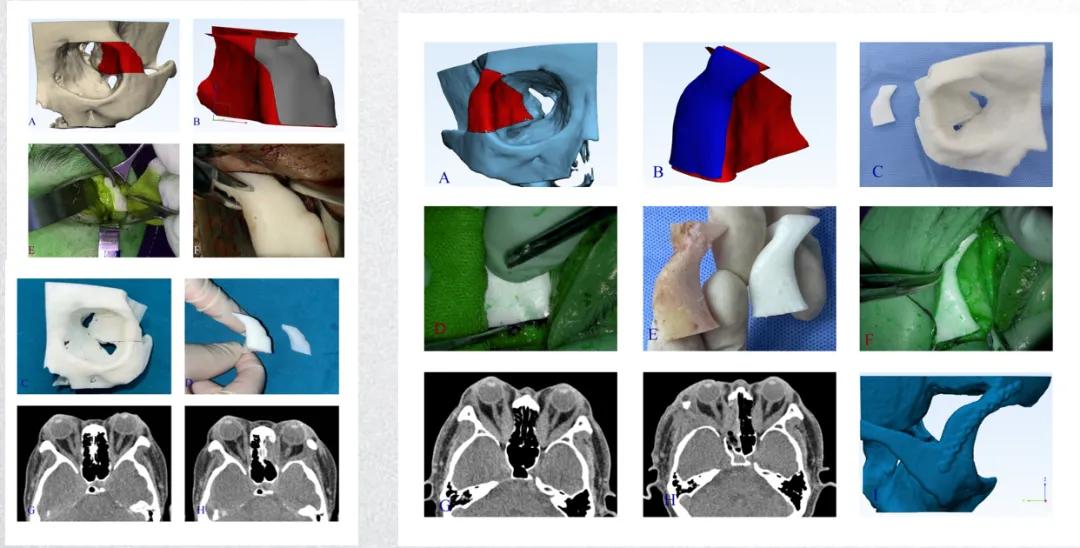

TED患者突眼严重时需行眶减压手术。对于外侧壁眼眶减压而言,最大化范围的骨壁去除有助于提高眼球突出和压迫性视神经病变症状的治疗效果。然而,外侧眼眶减压术中外侧骨壁去除范围越大,术中引起脑脊液漏、脑出血以及颅内感染等并发症的风险也将随之增大。要想在风险与获益之间找到一个平衡,就需要对手术的减压范围有精准的掌控。廖洪斐教授团队借助数字医学技术,将患者眶壁三维模型重建并进行虚拟手术演练,设计减压范围与截骨深度,并通过3D打印手术导板精准引导骨窗开放。数字化导板帮助术者在毫米级范围内完成外侧眼眶减压,避免减压过度或不足;在多例临床应用中,患者突眼平均回退值达到5mm以上,且并发症发生率低于传统方法。该研究表明数字导板可在毫米级范围内实现“最大减压、最小损伤”的平衡。

图2.A红色模型为截骨导板,B蓝色模型为定位导板,C三维打印的眼眶、截骨导板和定位导板,D术中借助定位导板确定外侧眶缘截骨位置,E截骨导板与颧骨瓣形态基本吻合,F术中借助截骨导板拟合修复截骨区域以检测截骨深度是否安全有效,G患者术前CT轴位图像,H患者术后CT轴位图像,I术后术眼外侧壁三维成像。

典型案例

患者女性,56岁,主诉双眼球突出1年,左眼视力下降3个月。

专科检查:

视力:右眼1.0,左眼指数/30cm;眼球突出度:20mm>--102mm--<21mm。诊断:1.左眼压迫性视神经病变(DON)2.双眼甲状腺眼病(右眼中重度,左眼极重度)。

手术方案:内镜下经鼻入路眶内侧壁减压+数字医学手术导板辅助下外侧眶减压术。

术后1周专科检查:

视力:右眼1.0 左眼1.0;眼球突出度:20mm>--102mm--<15mm;眼球各个方向运动可,无视物重影。

图3.患者术前与术后1周眼眶冠状位CT及视野检测结果。